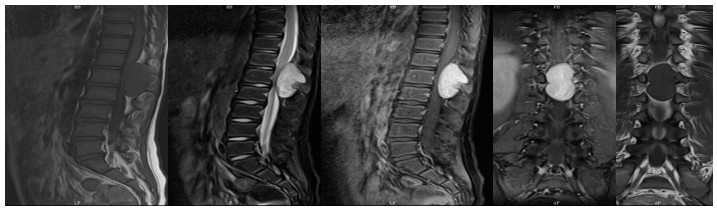

10歲小孩術(shù)前增強(qiáng)MR